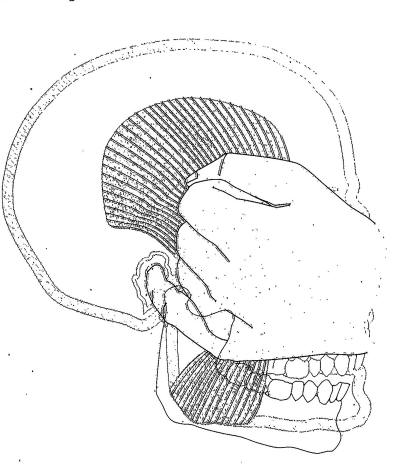

Palpación del músculo temporal |

|

El temporal también no presenta inconvenientes a la

palpación, dado que es un músculo menos poderoso que el

masetero, solemos pedirle al paciente que apriete sus

dientes co intervalos de descanso, para obtener respuesta

dolorosa a la palpación. |